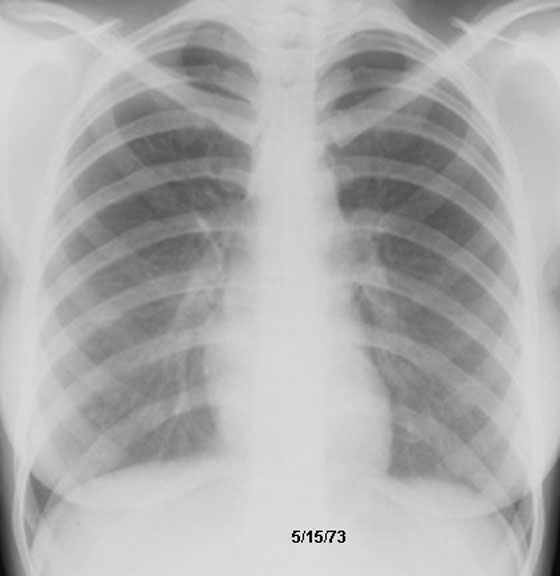

Sarcoidosis

Spontaneous Regression

Follow up film below.